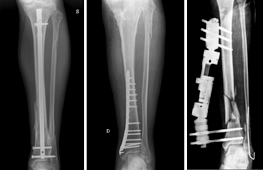

Durante l’intervento di osteosintesi i frammenti ossei vengono riallineati con appositi strumentari e vengono fissati con fili metallici, viti, placche, chiodi, fissatori esterni, ecc.

Ognuno di essi presenta specifiche peculiarità che ne determinano vantaggi e svantaggi. La scelta del mezzo di sintesi viene fatta dal Chirurgo in base a molteplici considerazioni (tipo di frattura, condizioni del paziente, qualità dell’osso). La maggior parte dei mezzi di sintesi è costituita da leghe metalliche, generalmente il titanio, che sono perfettamente biocompatibili. Essi possono, pertanto, rimanere in situ senza creare particolari problemi. Nei pazienti giovani o nel caso in cui i mezzi di sintesi diano fastidio perché troppo superficiali o perché determinano limitazione del movimento, si tende a rimuoverli dopo un tempo adeguato dalla guarigione (in genere dopo circa 18-24 mesi dalla frattura).

Nuovi strumentari e tecniche chirurgiche permettono l’osteosintesi mininvasiva che ha il grande vantaggio di limitare al massimo l’esposizione chirurgica e quindi accelerare la ripresa funzionale.

Quando una frattura non guarisce si parla di pseudoartrosi. Si definisce così perché la frattura, non guarendo, rende mobile (a volte senza dolore) il segmento formando una nuova articolazione. Le pseudoartrosi possono essere atrofiche, con scarse potenzialità biologiche, o ipertrofiche in cui la sola stabilizzazione del sito di frattura porta a guarigione l’osso.

Condizioni patologiche o stili di vita che aumentano il rischio di pseudoartrosi sono costituite dal fumo di sigaretta, dal diabete, da infezioni o gravi traumi che determinano la necrosi dei tessuti molli adiacenti all’osso (muscoli, fasce, tendini). Il trattamento di una pseudoartrosi prevede interventi complessi, utilizzando tecnologie avanzate sia per quanto riguarda gli strumentari e i presidi chirurgici sia nel campo della bioingegneria e della medicina rigenerativa (cellule staminali, biostimolatori/modulatori, ecc.).